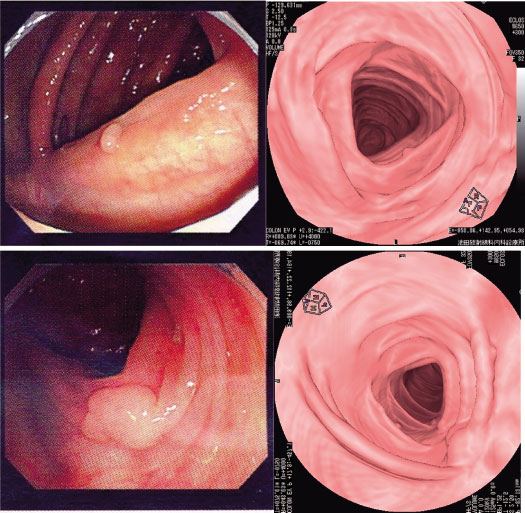

画像 5 左列は大腸ファイバー像/右列は仮想内視鏡画像

仮想内視鏡画像はCruising Eye View法という内腔を自動的に描出する手法に

より,消化管のみならず血管内腔や気管支内腔の表示も極短時間で行える。